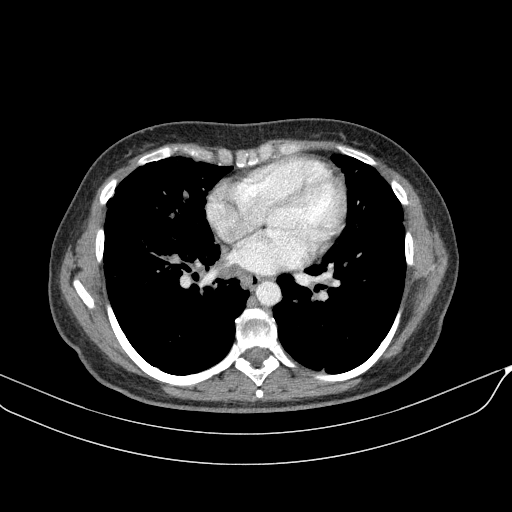

Targeted Slice 70 - Mediastinum Window Analysis (Generated vs Real Venous)

0.759

Mediastinum SSIM

45.2

Mediastinum RMSE

16.1

Mediastinum MAE

Average Mediastinum Window Metrics Across All Slices (40 slices) - Generated vs Real Venous

0.738

Mediastinum SSIM (Avg)

46.6

Mediastinum RMSE (Avg)

16.9

Mediastinum MAE (Avg)

Original VENOUS CT scan

Mediastinum window (WL 40, WW 400 β†’ Low βˆ’160, High +240)